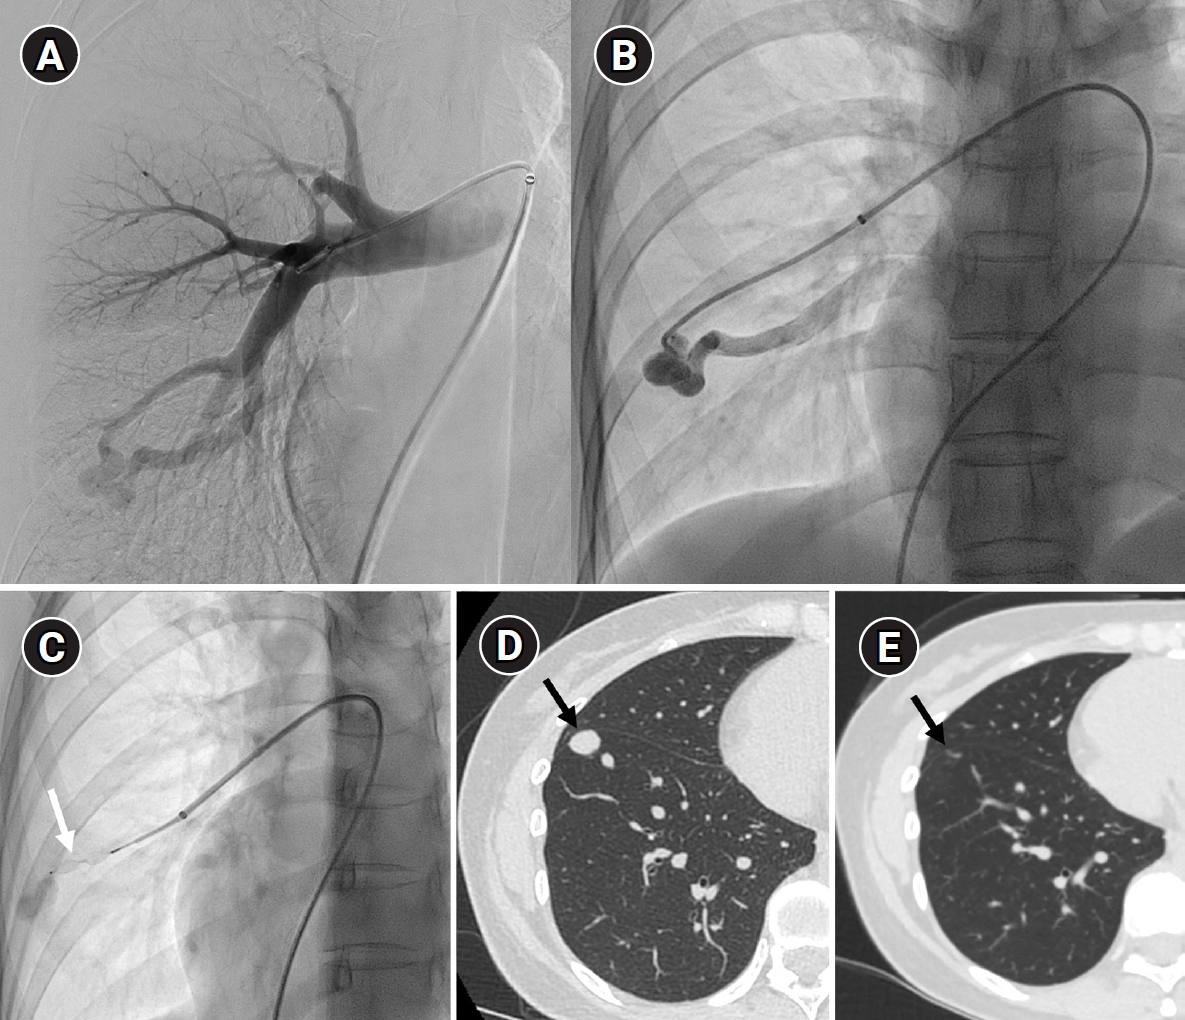

Fig. 10.

Images before and after embolization using a vascular plugs in a patient with a large pulmonary arteriovenous malformation (PAVM) in the left lower lobe. (A) In the time-resolved MR angiography, a PAVM in the left lower lobe exhibiting an early draining vein is observed. (B, C) The pulmonary arteriography also shows the same findings, and feeding artery embolization was performed using one Amplatzer vascular plug type II and six Amplatzer vascular plugs type IV devices. (D, E) In the 6-month follow-up time-resolved MR angiography, no rapidly appearing vein is observed in the arterial phase, and in the delayed phase, there is enhancement within the venous sac (arrow), which is considered part of the normal draining vein. (F–H) In the computed tomographic images taken at 1 month (F), 6 months (G), and 18 months (H) post-treatment, the thrombosed venous sac gradually diminishes, leaving only the normal draining vein (arrows) inside.

kjir-2026-00010f10.jpg